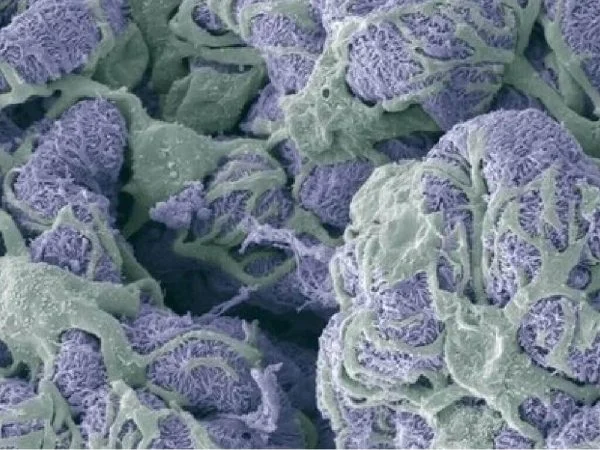

Image Credit: Newcells Biotech

aProximateTM is a highly advanced in vitro model of kidney PTCs that mimics physiological conditions. aProximateTM PTCs are derived from fresh human kidney tissue and grown on Transwells®. They remain well differentiated as a polarized cell layer with tight junctions.